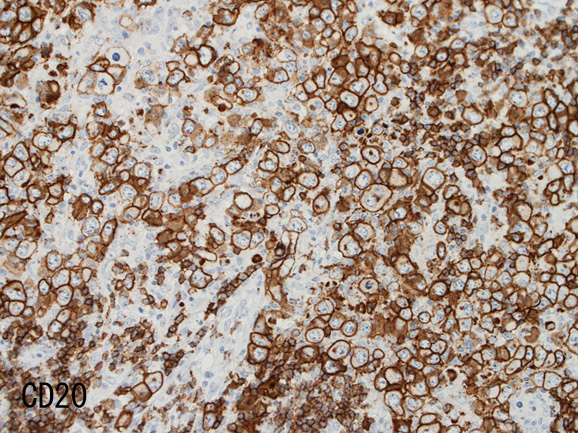

• RS細胞様巨細胞, LCLの大型細胞は B細胞マーカ(CD20, CD79a)が陽性。いずれかが消失することもある。通常腫瘍細胞の50%以上が陽性となりHodgkin病との鑑別点となる。

腫瘍細胞はCD20+, CD30+, CD15-, PAX-5+, Oct.2+, BOB.1+(Oct2, BOB1は田丸先生の染色結果), EBER-ISH+, EBNA2-